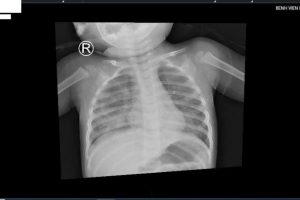

Vừa qua, bệnh viện Nhi Đồng Thành Phố tiếp nhận một trường hợp trẻ Ng. G. B. 12,5 tháng tuổi, nam, ngụ tại Tây Ninh, trong tình trạng khó thở tím tái. Bệnh sử...